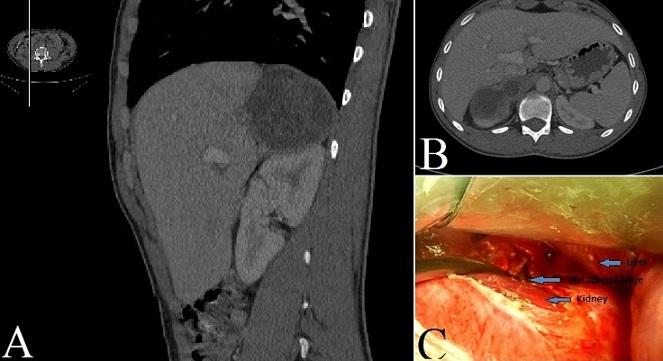

Primary hydatid cyst of the adrenal gland remains an exceptional localization. The adrenal gland is an uncommon site even in our country in which echinococcal disease is endemic. In the current literature, only 21 cases have been reported up to 2007. We report the case of a 56-year-old Moroccan man was admitted to our department for right flank pain with no particular irradiation that had started three month previously. His physical examination was unremarkable. A hematological examination was characterized by a slight augmentation of white blood cells (12 cells/mm3) and by eosinophilia (8% eosinophils). His blood biochemistry was normal. Computed tomography showed a cystic mass between the liver and the kidney with daughter cysts filing the lesion (Type III). After the radiological findings, the mass was presumed to be a primary adrenal hydatid cyst and surgical exploration was planned. Despite his negative serology tests, the diagnosis of a hydatid cyst of the adrenal gland was confirmed on surgical examination. Our patient underwent under costal laparotomy with surgical excision of his cyst and preserving the gland. Postoperatively, the patient was discharged from the hospital in a stable condition 5 days later. Our patient underwent therapy with albendazole (400 mg/day) hang 4 months, no recurrence has occurred after 16 months of follow-up.